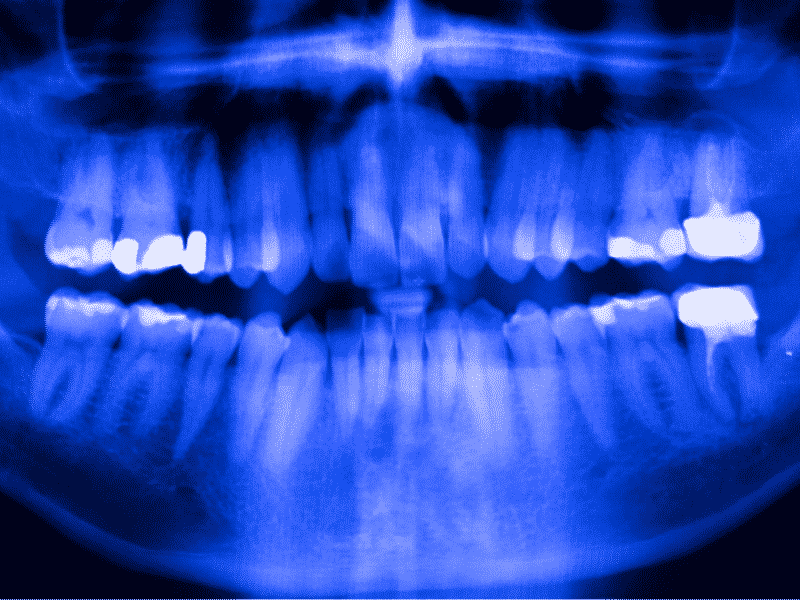

Laser dentistry uses an extremely focused beam of light to alter or remove tissue in small amounts and can be used in various procedures involving the inside of the mouth, including procedures for removing overgrown tissue, reshaping the gums, or whitening teeth. This type of Langley dental procedure is often ideal for children who are anxious or afraid of having dental work done.

While the traditional drilling method for treating cavities is effective and can help Langley patients remain healthy, it allows patients to remain comfortable while still providing the proper level of care. The invisible light beam used in this procedures is the most precise way to fix a cavity, which means that Langley dentists do not have to remove as much of the healthy tooth as they would when using a drill. Some types of lasers, such as water lasers, can also help reduce pain during the procedure by keeping the tooth hydrated. Instead of needles and drills, laser dentistry uses water, air, and light to treat cavities and to provide a less painful experience.

Laser dental procedures at JVR Dental in Langley, are safe and effective for treating cavities and other types of soft tissue treatments in both kids and adults and can be used without the need for sutures or anesthetic; however, patients with a lower pain tolerance can still opt to have an anesthetic used alongside the laser treatment.